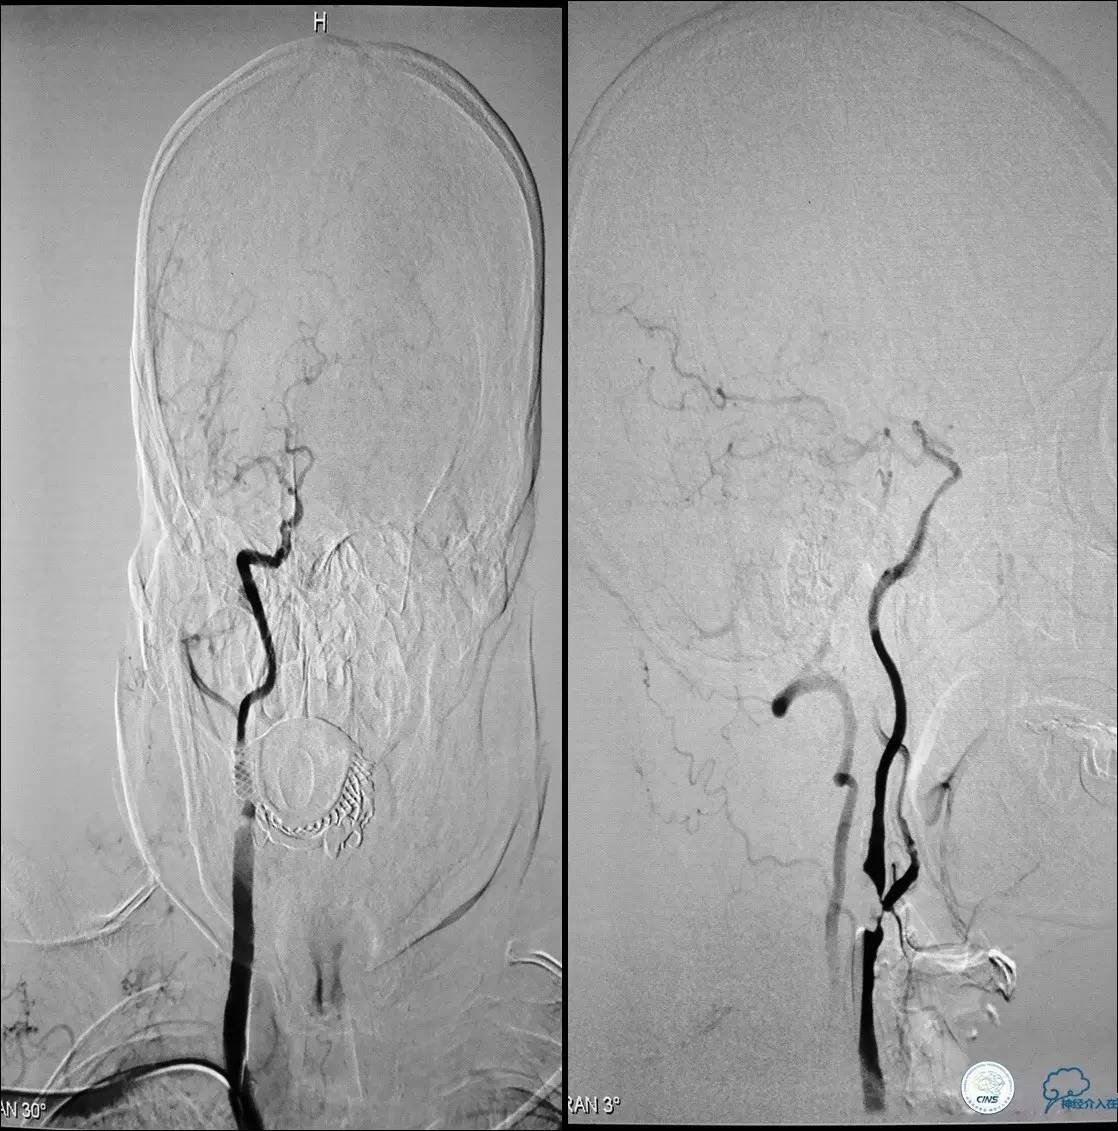

》辅助检查:颈动脉B超显示:左侧颈内动脉起始部狭窄 90%,右侧颈内动脉起始部80%。

Case 2

》男,74岁。

》主诉:突发左侧肢体抽搐伴口角歪斜两月余,右侧肢体抽搐三天余。

》查体:左上肢肌力Ⅲ级,左下肢肌力Ⅳ级,右侧肢体肌力Ⅴ级。

》既往史:高血压病史。